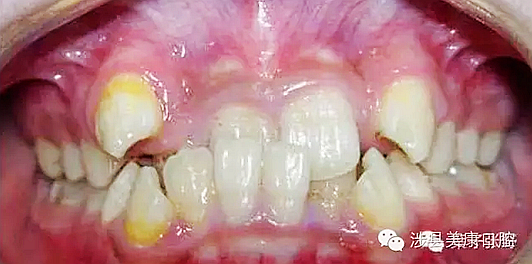

普通家長(zhǎng)看了這張牙片估計(jì)能看出來(lái)孩子的牙不好,但是究竟不好到什么程度呢,讓葉子姐告訴大家:

上圖孩子的乳牙感染已經(jīng)將下面骨感染到吸收消失,并且直接影響到了下面的恒牙胚,家長(zhǎng)們上點(diǎn)心吧。那些說(shuō)乳牙不用治療,換牙就會(huì)好的人(包括醫(yī)生)還是睜開眼睛看看吧,不要自欺欺人,更不要用自己的錯(cuò)誤誤導(dǎo)他人誤導(dǎo)大眾。